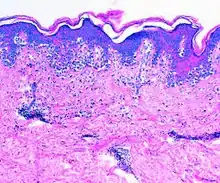

El diagnóstico se puede hacer analizando el aspecto distintivo de piel amarilla y gruesa en el área afectada. La elastosis solar también se puede diagnosticar mediante una biopsia de piel. Esto daría como resultado la baja de la eosina que mancha en las capas superiores de la piel dando por resultado una mancha de óxido. Algunas de estas lesiones si no se detectan a tiempo pueden llegar a convertirse en cáncer de piel. Ésta es una forma curable del cáncer si está cogida temprano, por eso se recomienda una investigación anual para prevenir riesgos.[3]